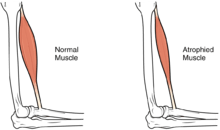

Complications

Complications of spinal cord injuries include pulmonary edema, respiratory failure, neurogenic shock, and paralysis below the injury site. In the long term, the loss of muscle function can have additional effects from disuse, including atrophy of the muscle. Immobility can lead to pressure sores, particularly in bony areas, requiring precautions such as extra cushioning and turning in bed every two hours (in the acute setting) to relieve pressure.[107] In the long term, people in wheelchairs must shift periodically to relieve pressure.[108] Another complication is pain, including nociceptive pain (indication of potential or actual tissue damage) and neuropathic pain, when nerves affected by damage convey erroneous pain signals in the absence of noxious stimuli.[109] Spasticity, the uncontrollable tensing of muscles below the level of injury, occurs in 65–78% of chronic SCI.[105] It results from lack of input from the brain that quells muscle responses to stretch reflexes.[110] It can be treated with drugs and physical therapy.[110] Spasticity increases the risk of contractures (shortening of muscles, tendons, or ligaments that result from lack of use of a limb); this problem can be prevented by moving the limb through its full range of motion multiple times a day.[111] Another problem lack of mobility can cause is loss of bone density and changes in bone structure.[112][113] Loss of bone density (bone demineralization), thought to be due to lack of input from weakened or paralysed muscles, can increase the risk of fractures.[114] Conversely, a poorly understood phenomenon is the overgrowth of bone tissue in soft tissue areas, called heterotopic ossification.[115] It occurs below the level of injury, possibly as a result of inflammation, and happens to a clinically significant extent in 27% of people.[115]